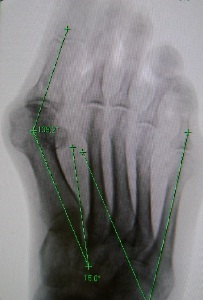

Radiografiile opri pacientul înainte și după intervenția chirurgicală gradul de platfus I

Radiografiile opri înainte și după tratamentul chirurgical al platfus gradul II

Radiografiile opri înainte și după tratamentul chirurgical al III-platfus grad

Radiografiile opri înainte și după tratamentul chirurgical al deformării al cincilea deget

Radiografiile opri înainte și după tratamentul chirurgical al deformarii cauzate de tratamentul greșit al platfus